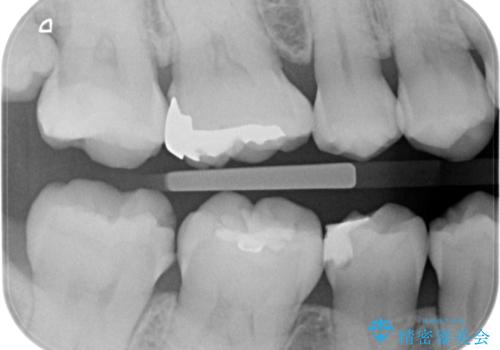

歯に食べ物が詰まる。

- 歯に食べ物が詰まるとの事で来院。

虫歯により歯が欠けていたので拡大鏡下で虫歯を除去した後、セラミックの詰め物で治療しました。

適合の良い詰め物が入りました。

セラミックスは虫歯の再発のリスクが低くなります。